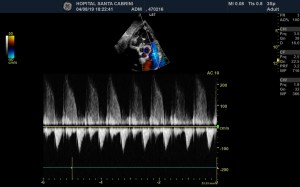

So I’m still trying to digest the RVOT Doppler physiology and working my hand at generating the best views and Doppler angles I can (See previous post on RVOT Doppler here). Not sure yet how this will fit in to my clinical practice but I think it’s worth shining a light into this murky pseudo-science of resuscitation. These guys are helping define its potential use… Naturally, this is bleeding-edge stuff. Use it to try to understand what’s going on with your patient’s physiology, don’t use this on board exams! My comments in bold.

Thus, the calculated pressure gradient rises and and the calculated resistance falls, but what has actually happened is that compliance has fallen, not “resistance”. More broadly, the term “impedance” is composed of compliance, resistance and something called the characteristic impedance [the Windkessels!]. Typically what abnormal RV Doppler shows you is that *impedance* has risen. At the end, you are often still left with the why? Impedance can rise when “true resistance “falls, but compliance also falls [as above] – yet the calculated RVSP/regurgitant jet will also rise. The linked papers are fantastic, but they both excluded patients with left heart disease, so you can be more confident that the RVOT abnormalities seen are related to true ‘pre-capillary’ problems. I’d be willing to bet [and if there’s data, i’d be interested to read it] that patients with pure WHO II pulmonary venous hypertension have very similar abnormalities on the right side. The key means to distinguish – as Korbin talks about – is really looking at the left heart [E/e’] and clinical context to get a better sense of what’s going on.

What would also be interesting would be to look at acutely “decompensated” true left heart disease in volume overload and correlated with RVOT morphology and great vein Doppler velocimetry. My guess is that as you decongest the pulmonary veins [increase their compliance] that the RVOT envelope “pulsatility” goes away [the RV ejection envelope appears more rounded] as does the venous pulsatility in the great veins and intra-renal veins! It’s all about energy transfer … moving away from excessive potential energy trapped in distensible structures [i.e. congestion] to kinetic energy [normal, forward blood flow]